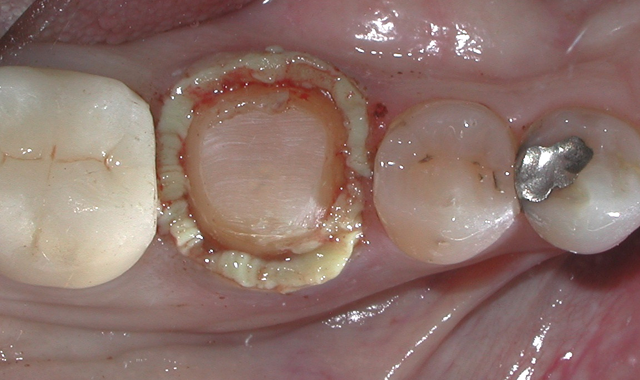

I completed the occlusal preparation with a ball diamond bur (Premier Dental, Solo #801023C), which provided the laboratory with adequate central fossa reduction to create sufficient thickness of material for strength and esthetics while allowing enough material for adjustment (Fig. 8).

Fig. 8 Fig. 9

Beveling is important to the success of the crown, and PFM crowns lend themselves nicely to this preparation design. The bevel adds 1.0–1.5 mm of additional tooth structure to provide needed ferrule for resistance to lateral forces. In addition, creating a bevel reduces the circumferential width of the tooth in the critical cervical area, thereby decreasing the emergence profile of the crown.6 Shoulder bevel preps were originally designed to mitigate metal distortion during porcelain fusion, and although this hasn’t been proven not be clinically relevant (finish line form doesn’t significantly affect the fit of metal ceramic crowns), I’ve had success with this preparation design on teeth that I crown.7

To create a circumferential bevel for tooth #30, I used a flame diamond (Premier Dental, Solo #862012C) (Fig. 9). I then carefully inspected for tissue attachment to the bevel region, as any tissue left adhering will negatively affect my impression. Any tissue was then removed with either a periodontal curette or a rotary instrument.